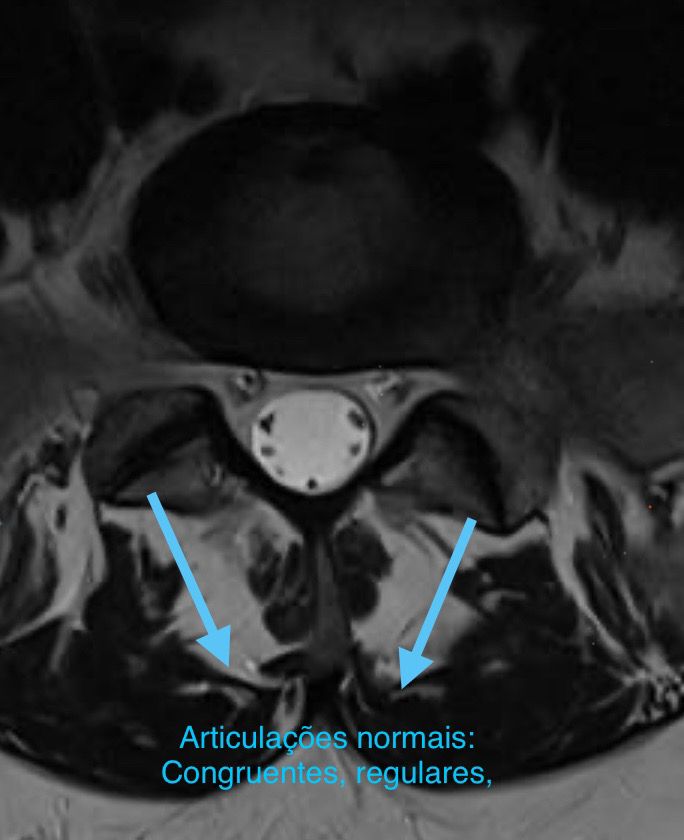

Na imagem, é possível ver as alterações a articulação da coluna em um paciente com artrose.

Quando saudável, articulação da coluna apresenta contorno regular e espaço para a passagem dos nervos.